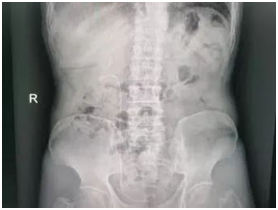

术前

输尿管鞘是什么名医动态|以柔克刚,无创取石——我院泌尿外科开展可弯曲负压吸引鞘+输尿管软镜钬激光碎石术_https://www.jmylbn.com_新闻资讯_第3张